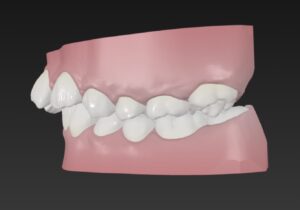

🔶初診時🔶

右

でっ歯さん

歯並びガタガタのそうせいを気にして

マウスピース矯正希望で来院